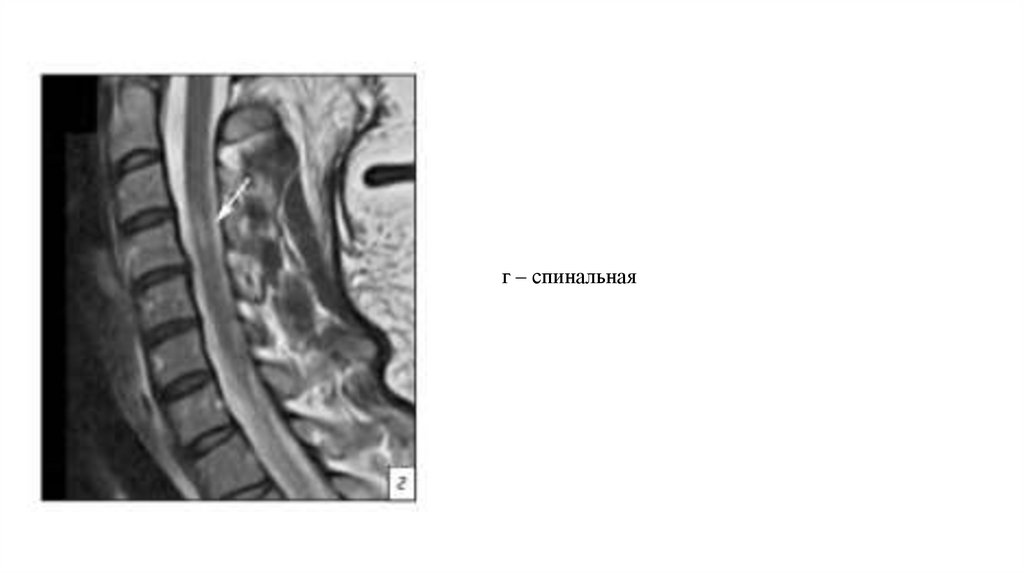

г – спинальная

К характерным МРТ-признакам относятся наличие очага демиелинизации в прехиазмальных

отделах зрительных нервов и протяженных (более двух сегментов спинного мозга) очагов

поперечного миелита, преимущественно в грудном отделе позвоночника. При этом очаги и

соответствующая симптоматика в большинстве случаев появляются не одновременно. При

болезни Девика очаги в спинном мозге отличаются от таковых при РС

длинносегментарностью, в аксиальной плоскости они занимают более половины поперечника

спинного мозга, имеют более высокий сигнал на Т2-ВИ, приближаясь к интенсивности

ликвора, а также тропны к грудному отделу в отличие от РС, для которого более характерно

поражение шейных сегментов на начальных стадиях. Наряду с изменениями в зрительных